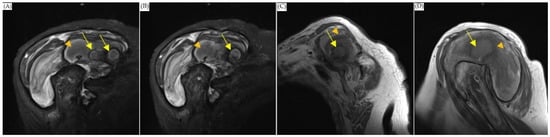

The orthopedist then followed up with an MRI scan on the first day after admission and noticed a 3.3 × 8.2 cm abscess in front of the humeral head extending across subacromial and subdeltoid space with intra-articular involvement. The scan also showed a 1.7 cm inflammatory pseudotumor (IPT) within the supraspinatus muscle, and osteomyelitis of the humerus (Figure 1). The antibiotics vancomycin and ceftriaxone were prescribed upon admission. On the sixth and thirty-second days after the MRI scan, computed tomography (CT)-guided pigtail drainage was arranged, which only mildly decreased the pain and swelling (Figure 2). Because the improvement to the shoulder mass and the symptoms was rather slow, a surgical shoulder debridement procedure was arranged to remove blood clots and insert antibiotic beads. During the operation, a pulsatile tumor was noticed. The orthopedist did not complete the tumor resection or tumor biopsy for the risk of tumor rupture combining uncontrolled bleeding. Under the impression it was a pseudoaneurysm, the orthopedist team decided to complete the debridement without touching it.

MRI of shoulder. (A,B) were coronary plane, (C,D) were sagittal plane. All the images showed: 1. An encapsulated cystic mass extending across subacromial and subdeltoid space (arrowhead), which was suggestive of abscess. 2. Enhancing nodule within the supraspinatus muscle, which was suggestive of inflammatory pseudotumor (arrow).